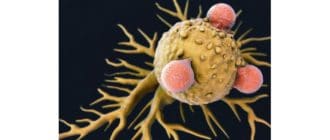

ノースカロライナ州ダーラムのデューク大学の研究者は、がん細胞を殺す新しい方法を発見したかもしれない。 チームは、脳神経外科の教授であるマティアス・グロミエ博士と外科学部の免疫学者であるスミタ・ナイール教授が共同指導しまし […]